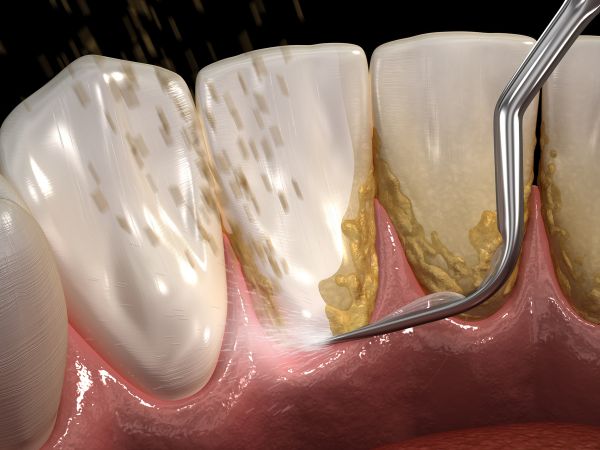

El sarro, también conocido como cálculo dental, es la acumulación endurecida de placa bacteriana en los dientes. Esta calcificación ocurre debido a los minerales presentes en la saliva. El sarro se forma principalmente en la línea de las encías y en las áreas difíciles de limpiar, proporcionando una superficie rugosa que facilita la acumulación de más placa bacteriana.

El sarro dental se desarrolla cuando la placa bacteriana no se elimina adecuadamente mediante una correcta higiene oral. La placa es una película pegajosa e incolora que se forma constantemente en los dientes, especialmente después de comer alimentos azucarados. Si no se retira, la placa se endurece y se convierte en sarro en tan solo 24 a 72 horas.

- Limpieza Profesional: Visita a tu dentista regularmente para una limpieza dental profesional. Solo un dentista puede eliminar el sarro una vez que se ha formado. Se recomienda una limpieza profesional cada seis meses.